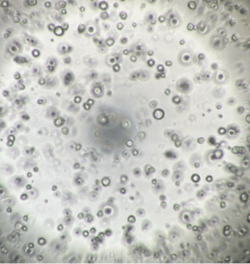

InnoCell(R)プレートシリーズは、体外での細胞培養において、各々の細胞に適した酸素供給を実現できます。その機能により、長期間、元気な細胞を体外で培養できるうえ、スフェロイドの内部で起こる壊死を軽減できるため、正確な医薬品のスクリーニング結果の提供に期待されています。また、これまで体外で培養が難しかった、ヒト膵がん患者由来オルガノイドの増殖性の向上により、個別化医療における患者さんに適した医薬品の早期提供の可能性も期待されています。

さらに、プレートへの薬剤の吸着性が低く、ガラスに匹敵する蛍光観察性能を備えています。試験に供した薬剤が正確に細胞へ作用し、細胞の構造、機能などが可視化できる価値も認められています。